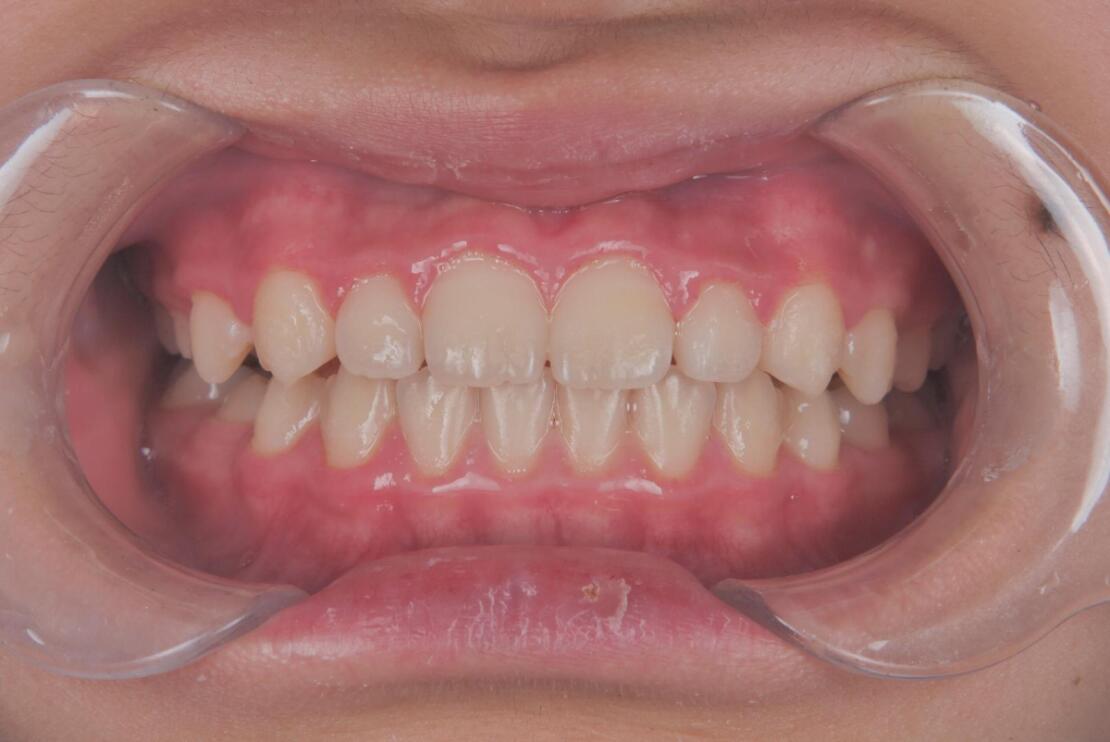

AFTER

| 年齢・性別 | 9歳男児 |

|---|---|

| 主訴 | すきっ歯とガタガタが気になる |

| 施術内容 | プレオルソ+インビザラインファースト |

| 治療期間 | 1年半 |

| 費用 | 594,000円(税込) |